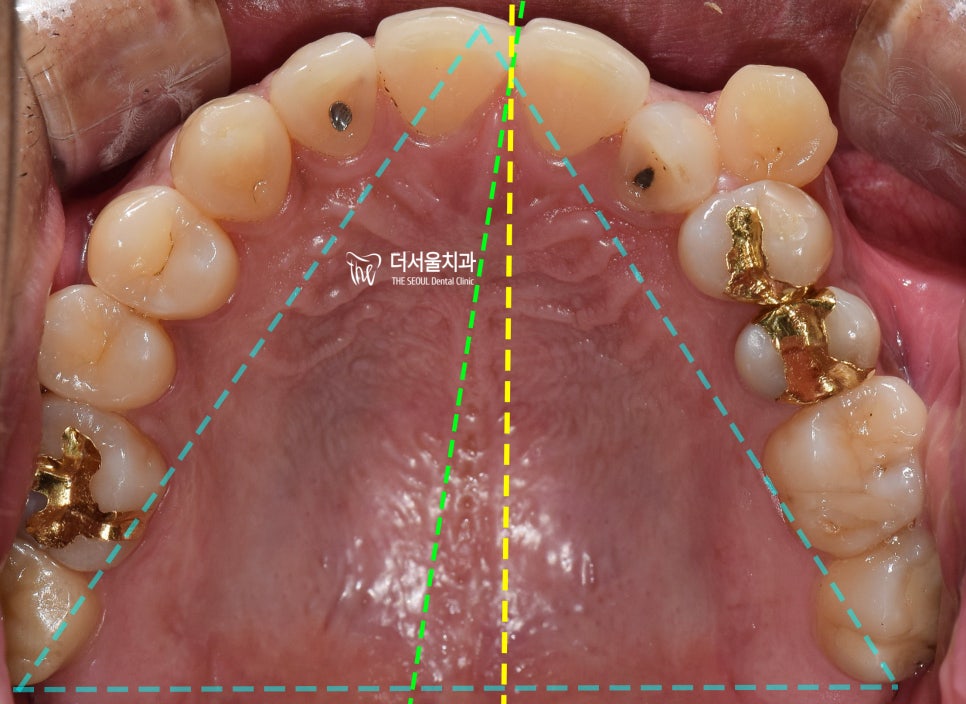

이건, 교합면에서 봤을 때

더 명확히 드러나게 됩니다.

상악 악궁에 배열 된 치아들은,

살짝 한쪽으로 쏠려 있는 것을 볼 수 있습니다.

어금니의 위치는 서로 대칭이 되는데,

앞니쪽으로 갈 수록 악궁의 형태가

조금 비대칭이 되는거죠.